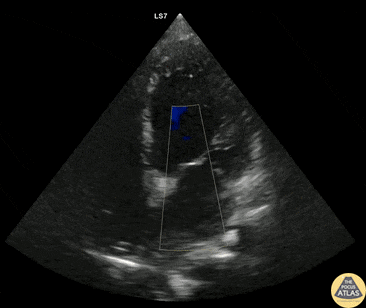

Valvulopathy - Severe Mitral Regurgitation

60s M with PMH ischemic cardiomyopathy and CHF presented with multiple episodes of syncope. The initial workup was unrevealing so POCUS was performed. These color doppler images demonstrate severe mitral regurgitation as seen as a multicolored retrograde jet from the mitral valve during systole. This patient was admitted for further workup of his syncope and telemetry monitoring given the structural heart disease and concern for underlying dysrhythmia. Dr. Nhu-Nguyen Le, Fellow Denver Health Ultrasound Fellowship